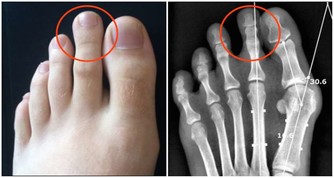

跟癌症、心腦血管疾病相比,關節炎似乎算不上多麼致命的疾患,然而它發作時的痛苦程度,讓所有患者一想起來就心有餘悸。想想手部、手腕、腳部關節疼痛、腫脹、僵硬的滋味吧,你一定不會喜歡的。

由於維生素C是一種天然抗氧化劑,所以可以降低炎性細胞因子水平,並防止關節破壞,因而有助於減少關節的疼痛、僵硬和腫脹。

當醫生每週兩次,給因為關節炎而疼痛的患者靜脈注射維生素C,持續四周之後,他們的疼痛消失了。而另外一些研究表明,維生素C水平低的人,出現類風濕性關節炎的可能性,比體內維生素C水平充足的人,要高出三倍。